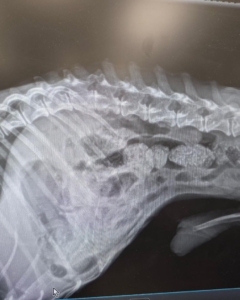

Update on Our little miracle Chihuahua. He looks like he has some fused vertebrae, whether previous trauma or disk problem. He’s very malnourished so he will be on special food. His remaining teeth will need a dental. He is getting medication for pain management.